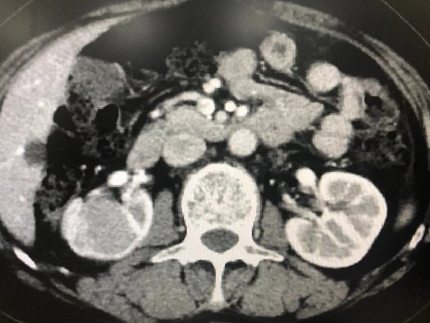

病例六,69岁女性,发现双肾占位10年。10年前于外院发现双肾占位,考虑错构瘤,右肾肿物4cm,定期观察。2周前复查CTU增强提示双肾多发错构瘤,大者位于右肾下极,7.3cm×3.9cm×6.7cm,左侧大者约4.3cm×4.3cm。行机器人辅助腹腔镜双肾部分切除术,术者:张树栋教授、郝一昌教授。术中右肾肿瘤位于肾脏下极,且与肾门关系紧密,仔细分离需小心输尿管损伤。